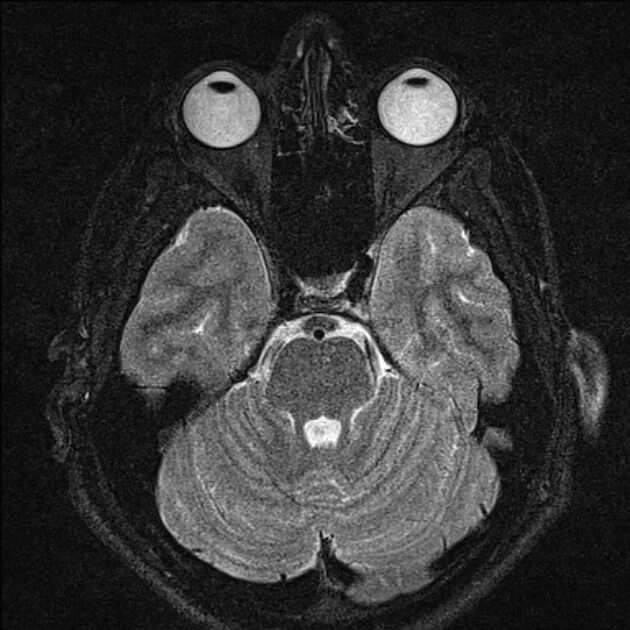

Мрт орбит и зрительных нервов